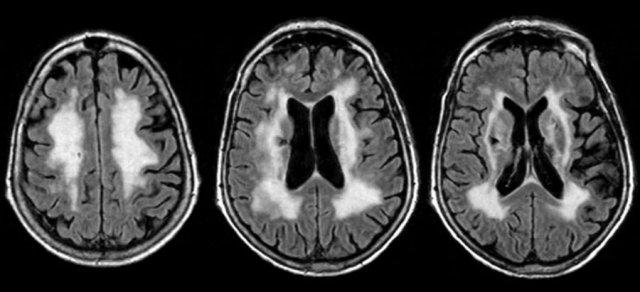

ADEM

Viêm não tủy lan tỏa cấp tính (ADEM) là một chẩn đoán phân biệt quan trọng khác của MS.

Đây là bệnh mất myelin qua trung gian miễn dịch, đơn pha, thường gặp ở trẻ em sau nhiễm trùng hoặc tiêm chủng.

Nhiều bệnh nhân có kháng thể kháng MOG (MOG = Glycoprotein myelin oligodendrocyte).

Trên MRI, thường có các tổn thương lan tỏa và tương đối đối xứng ở chất trắng trên và dưới lều, có thể ngấm thuốc đồng thời.

Thường có tổn thương ưu thế ở chất xám vỏ não và chất xám sâu của hạch nền và đồi thị.

Đây là hình ảnh FLAIR và T2W cắt ngang của một bệnh nhân trẻ mắc ADEM – lưu ý tổn thương lan rộng ở chất xám vỏ não và chất xám sâu, bao gồm đồi thị.

Đây là một trường hợp ADEM khác.

Lưu ý tổn thương ở hạch nền và cuống tiểu não giữa.

Lưu ý sự tương đồng với hai trường hợp còn lại.

Sự khác biệt giữa ADEM và MS được tóm tắt trong bảng.